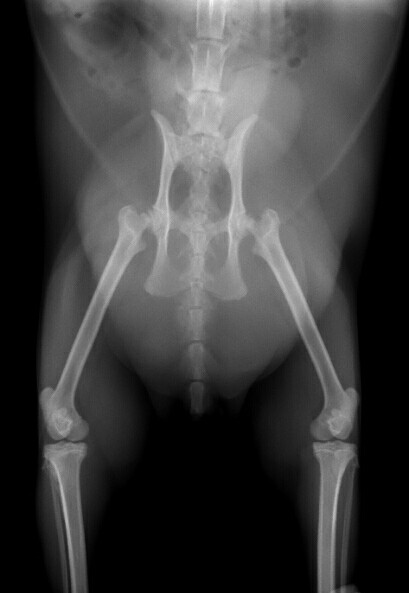

• 흉, 복부 방사선 검사 방사선 검사는 골격계의 이상을 진단하는 기초검사입니다. 방사선 검사를 통해 골격계의 선천적 이상 등을 진단하게 됩니다. 흉부 방사선 사진을 통해 기관의 이상 유무 판결, 심장 크기 및 위치의 변화 등을 진단하게 됩니다. 복부 방사선을 통해 방광의 결석, 복강 실질장기의 크기 및 위치 변화 등을 진단할 수 있습니다. 또한, 드물게 발생하는 선천적 결손증의 일부를 진단하게 됩니다.

• 흉, 복부 방사선 검사 노령화가 진행됨에 따라 종양성 질환도 증가하게 됩니다. 종양의 발생 유무와 전이여부를 판단하기 위해 흉강과 복강 방사선 사진이 필요합니다. 암컷의 경우 장년기에 자주 발생하는 질환이 자궁축농증과 유선의 종양입니다. 방사선 사진으로 질병의 조기진단이 가능합니다. 수컷의 경우는 전립선의 이상으로 발생할 수 있는 질환을 진단할 수 있습니다. 종양과 비뇨생식기계질환의 조직 진단으로 건강한 생활을 영위할 수 있도록 도움을 주게 됩니다.

• 흉, 복부 방사선 검사 노령기의 질환 중 상당수가 종양성 질병과 관련이 있습니다. 정기적인 방사선 검사를 통해 종양성 질환의 발병 유무 및 전이여부를 평가합니다. 심장의 외형변화, 폐 실질의 이상 변화 등을 검사하고 지속적으로 관리하여야 합니다. 체표의 종양성 질환은 눈으로 관찰이 가능하지만 심부의 종양은 관찰이 어렵습니다. 심부의 종양성 변화를 비교적 쉽게 관찰할 수 있는 검사법이 방사선검사입니다. 노령기는 약 6개월단위 정기 검사가 필요합니다.